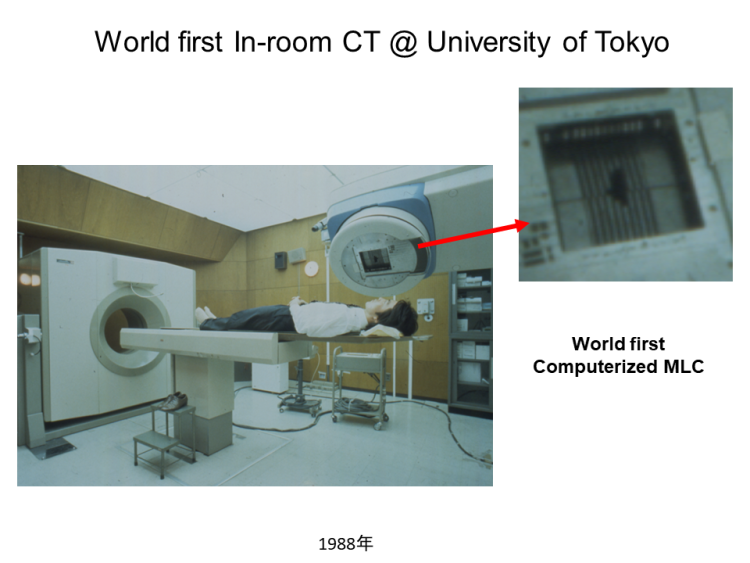

中川:ところで、いまではIGRTって当たり前のようにされているけど、あれを世界で最初にやったのは東大なんですよ。東大、というか、私です。私の学位論文でした。

中川:まずタングステン酸カドミウムクリスタルからフォトダイオードを作って、それを256個並べて 検出器を作るんですね。それで治療器の上でCTをとれる機械を開発しました。マルチリーフコリメーターも開発して。同室CTといって、診断CTと治療CTを同じ部屋に置くわけです。だから今では当たり前にやっているIGRTの技術だけど、私が学位論文でやったのが最初だったというわけです。1990年頃 、正確には学位論文になったのは1989年ですから、そのころの話です。その日のうちに帰ったことなんてなかったですよ。

中川:CTそのものですよ。三菱電機と一緒に開発したんです。

中川:私が計測から検証までなんでもひとりでやらざるを得なかったので、だいたいのことはできたのですが、いかんせん医学物理士がいない。だいたいのことはわかっても、私は物理を修めているわけではないので細かいことはわからないこともある。すると海外に売っていくのは無理です。それに、放射線治療はアングロサクソンの世界なんです。世界の文明の在り方の問題で、彼らは日本製の技術に本能的な忌避感を感じるように思います。それで結局、その機械は、三菱電機からエレクタに買収されていきました。